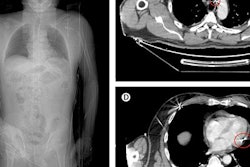

The researchers, led by Dr. Alessandro Napoli, PhD, from Sapienza University of Rome, investigated the potential utility of CT-guided pulsed radiofrequency (pRF) in previous research, which they presented at RSNA 2017. This minimally invasive interventional radiology procedure involves inserting a needle and probe at the site of injury using CT guidance and then delivering pulsed energy to the affected nerves for 10 minutes.

Expanding their work in this area, Napoli and colleagues performed CT-guided pRF on 128 patients with lumbar disk herniation who did not respond to traditional treatment with steroid injection.